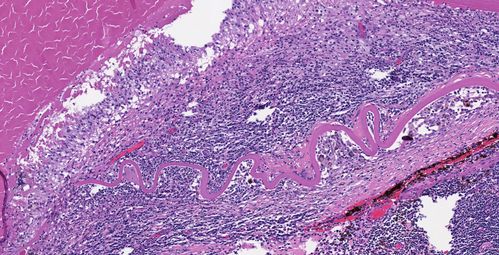

Phacoantigenic Reaction

Picture shows a Left eye enucleation with H&E staining.

Anterior capsule of lens is broken with evidence of granulomatous inflammation.